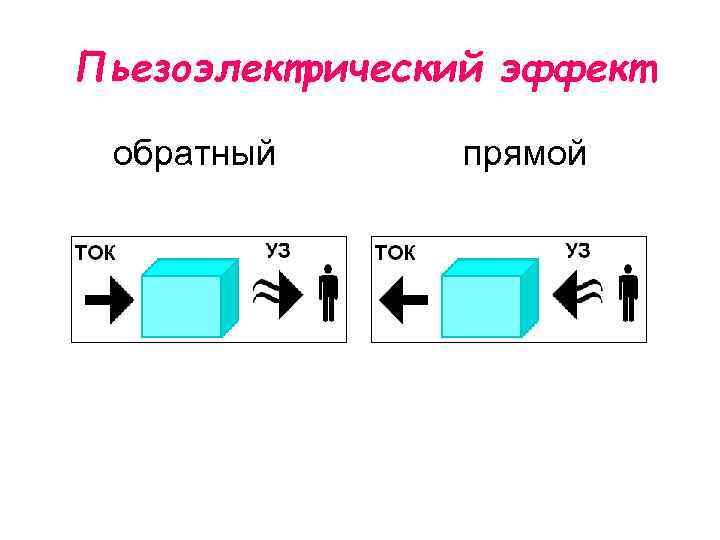

Пьезоэлектрический эффект обратный прямой

Пьезоэлектрический эффект обратный прямой

• Прямой эффект открыт братьями Жаком и Пьером Кюри в 1880 г. • Обратный эффект был предугадан в 1881 г. Липпманом на основе термодинамических соображений и в том же году экспериментально подтверждён братьями Кюри.

• Прямой эффект открыт братьями Жаком и Пьером Кюри в 1880 г. • Обратный эффект был предугадан в 1881 г. Липпманом на основе термодинамических соображений и в том же году экспериментально подтверждён братьями Кюри.

• Получение ультразвуковых волн базируется на обратном пьезоэлектрическом эффекте • Детектирование отраженных ультразвуковых сигналов базируется на прямом пьезоэлектрическом эффекте

• Получение ультразвуковых волн базируется на обратном пьезоэлектрическом эффекте • Детектирование отраженных ультразвуковых сигналов базируется на прямом пьезоэлектрическом эффекте